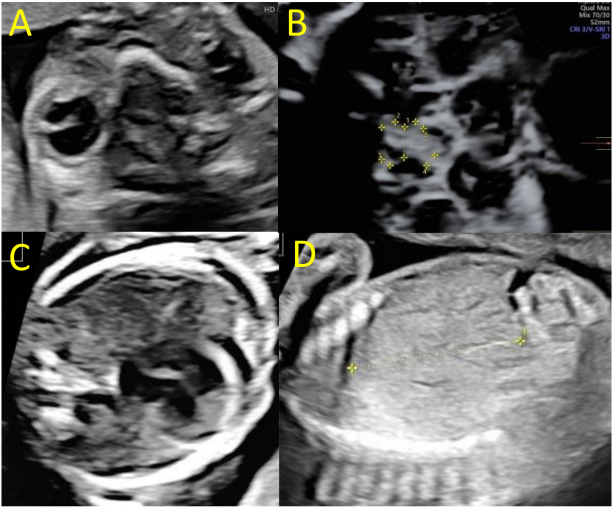

22 wg的超声检查证实胎儿严重的双侧心室肥大,伴有脑室周围充血、皮质变薄、皮质带不规则、尾状核畸形(包括钙化)、脑周间隙扩大、第三脑室扩张、透明隔腔破裂、层状胼胝体和小脑发育不全(主要影响小脑半球,小脑横径20mm)(图1)。

图1. 孕22周胎儿神经声学造影

胎儿大脑中动脉的收缩速度为40 cm/s,相当于胎龄中值(mom)的1.4倍。观察到右侧单侧小眼球,脑外检查显示胎儿生长受限(FGR),估计胎儿体重为450克,低于胎龄的第三百分位数。